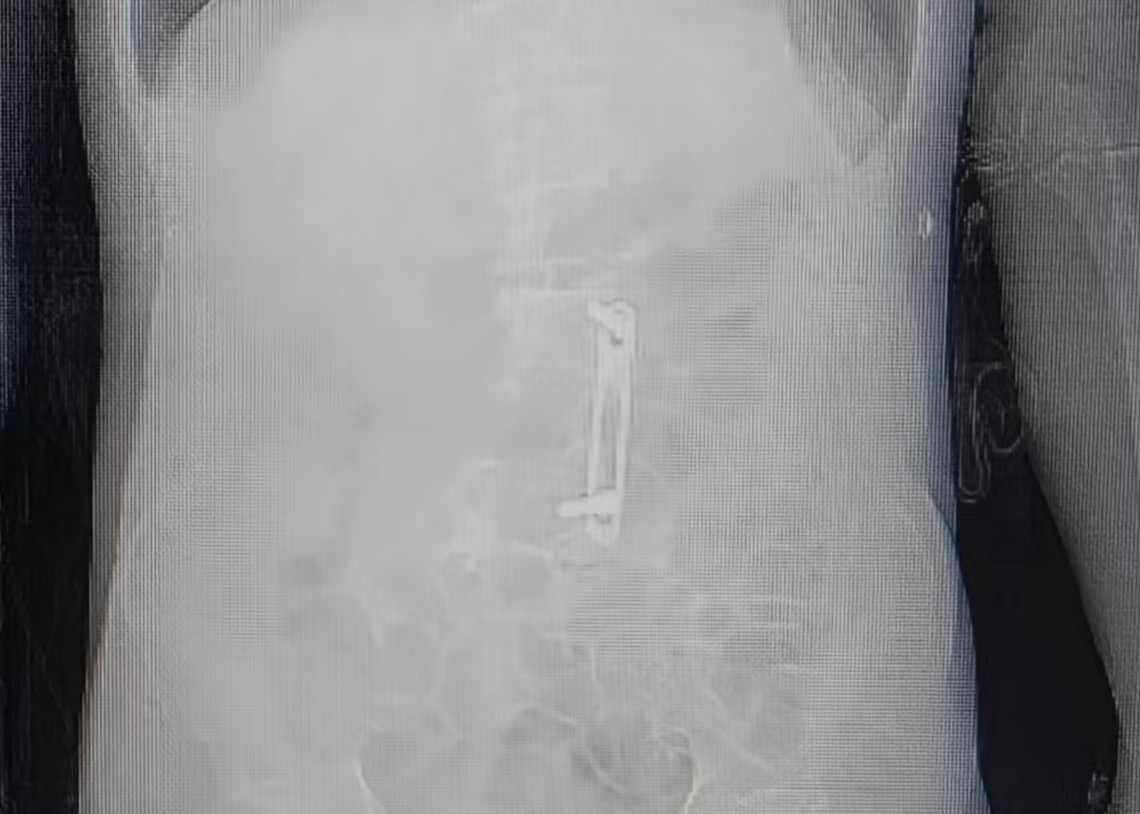

在团队仔细研读患者腰椎CT影像后发现,腰2-3间隙结构仍保持完整,为单侧腰麻的实施提供了可能。

(患者腰椎内固定术后,腰2-3间隙结构仍保持完整)